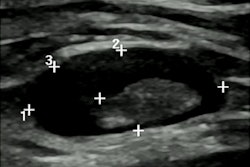

Screening mammography performed in a 44-year-old woman with a positive family history for breast cancer (mother and aunt), bearing implants for aesthetic purposes. Mammography (A) was considered negative. Breast ultrasonography was also performed because of her family history and high breast density (ACR category D). While ultrasonography was negative for both breasts, multiple round, enlarged, hypoechoic lymph nodes (measuring up to 1 cm in axial diameter), with a thickened (< 3 mm) cortex, were seen in the left axilla (B). There were no skin changes and there was no history of any infection or trauma. On the right side, axillary lymph nodes were normal. Because of her family history and the presence of breast implants, MRI was performed (C = apparent diffusion coefficient map; D = T2-weighted short-time inversion recovery; E = fat-saturated contrast-enhanced T1-weighted gradient-echo). No suspicious mass or nonmass lesions were seen in both breasts. Implants displayed no signs of rupture (not shown). In the left axilla, multiple enlarged lymph nodes were well visible in D and E (red circles); on the apparent diffusion coefficient map (C), they mainly exhibited low signal (restricted diffusivity). When an ultrasound-guided biopsy of the most suspicious lymph node was proposed, the patient mentioned that she had had a Comirnaty COVID-19 vaccination (Pfizer-BioNTech) one week before in the left arm. The attending radiologist was more than surprised to hear this, as at that time, a COVID-19 vaccination was only administered to people older than 70 years. Follow-up performed four weeks after the second vaccination was negative and showed no residual enlarged lymph nodes.Further research and adherence to evidence-based recommendations are paramount to standardize the management of findings, avoiding unnecessary additional imaging, and invasive procedures, the authors concluded.